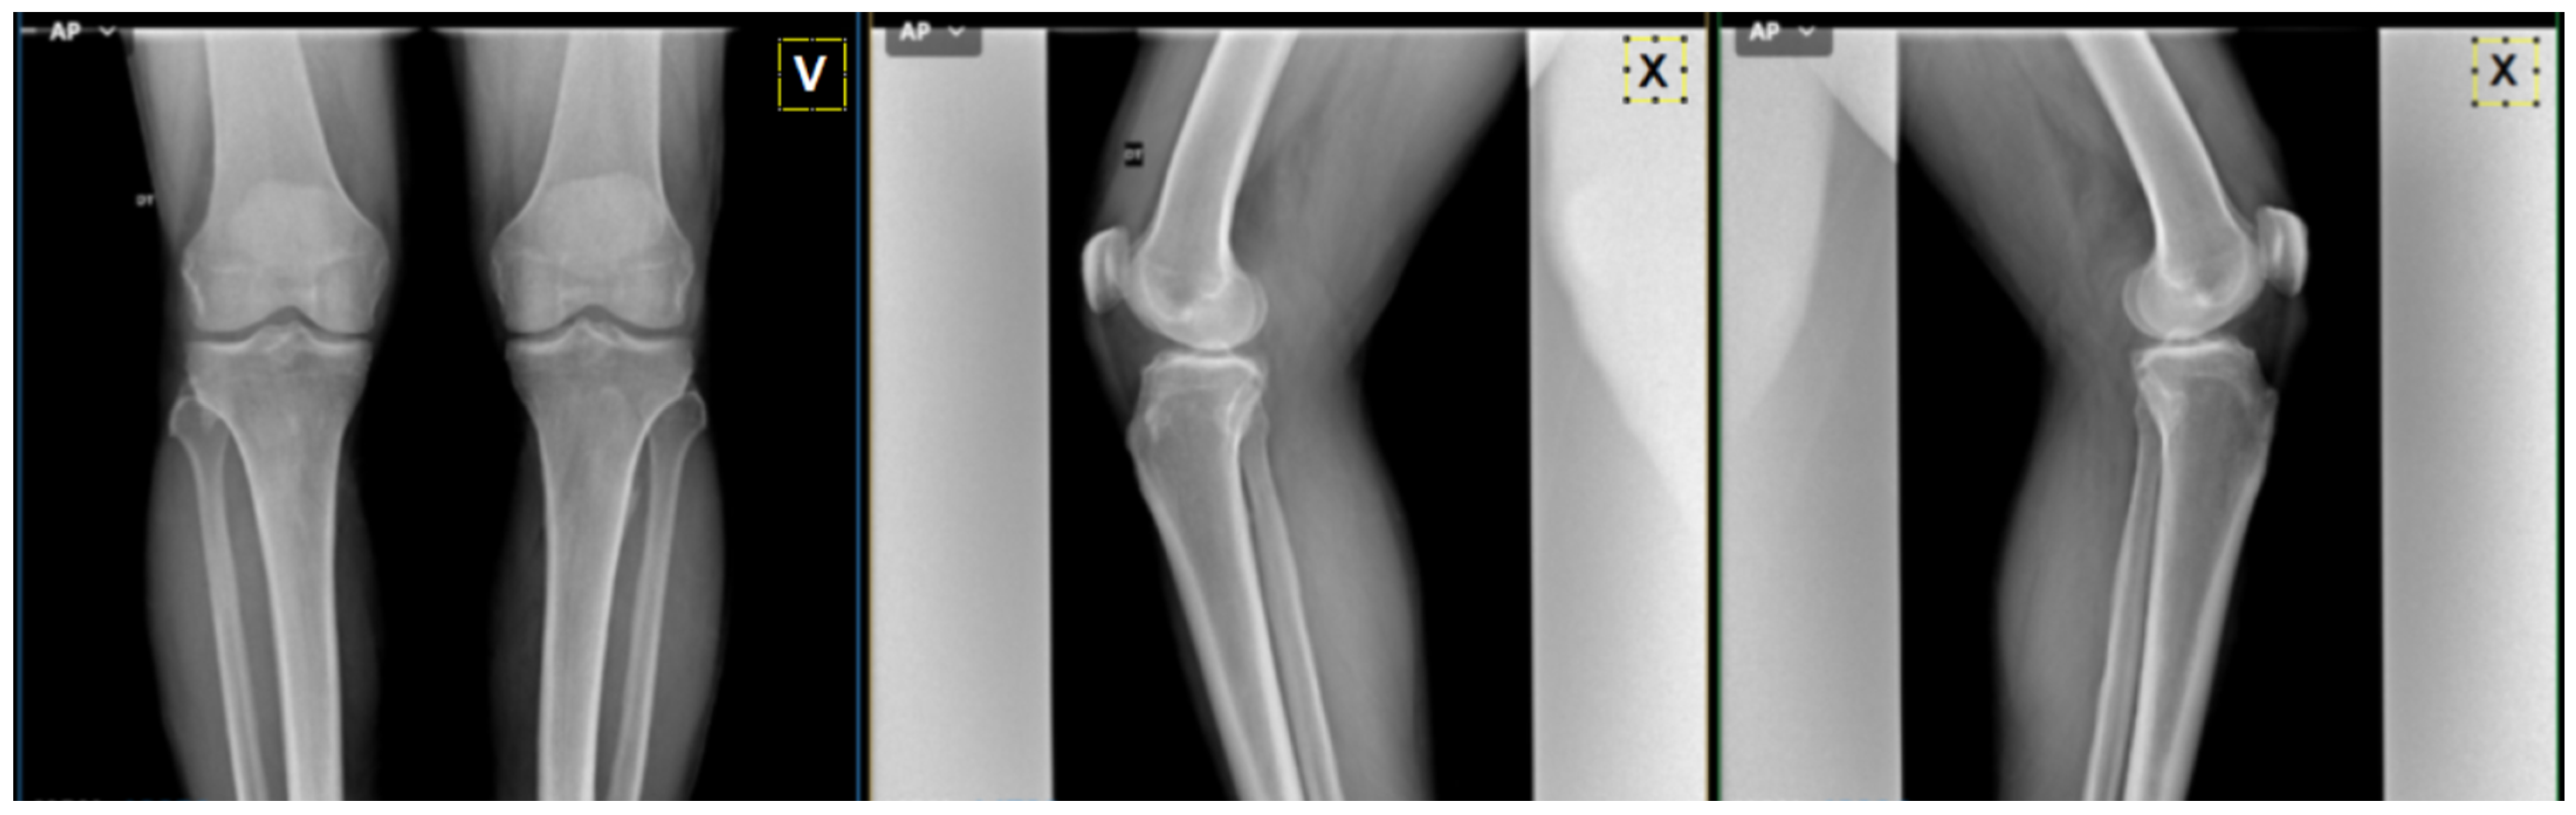

3.2. Preprocessing